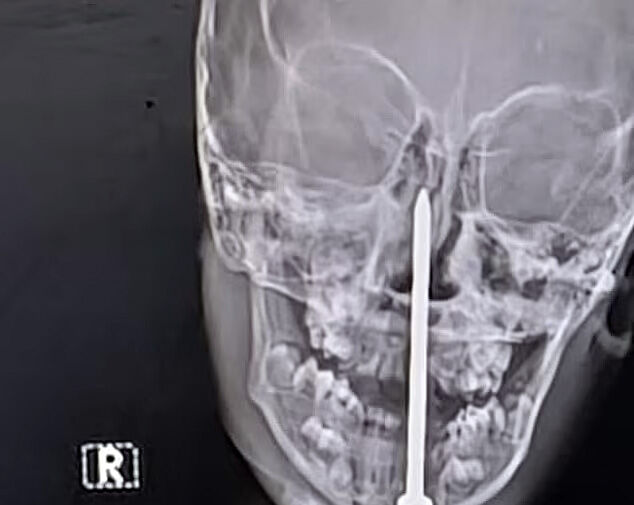

Семилетний мальчик из штата Раджастан перенес сложную нейрохирургическую операцию, во время которой врачи извлекли гвоздь длиной семь сантиметров из его мозга, пишет Daily Mail.

По данным местных СМИ, инцидент произошел, когда мальчик играл рядом со строительной площадкой, где споткнулся и упал носом на гвоздь. Его срочно доставили в больницу в Джайпуре, сделали компьютерную томографию и обнаружили, что инородный предмет почти на пять сантиметров проник в мозговую ткань.

Хирургическая бригада под руководством доктора Санкета Шармы провела более чем четырехчасовую операцию по удалению гвоздя. По словам врачей, чудом затронутыми оказались только лобные доли мозга, отвечающие в основном за когнитивные функции, а не за жизненно важные центры.